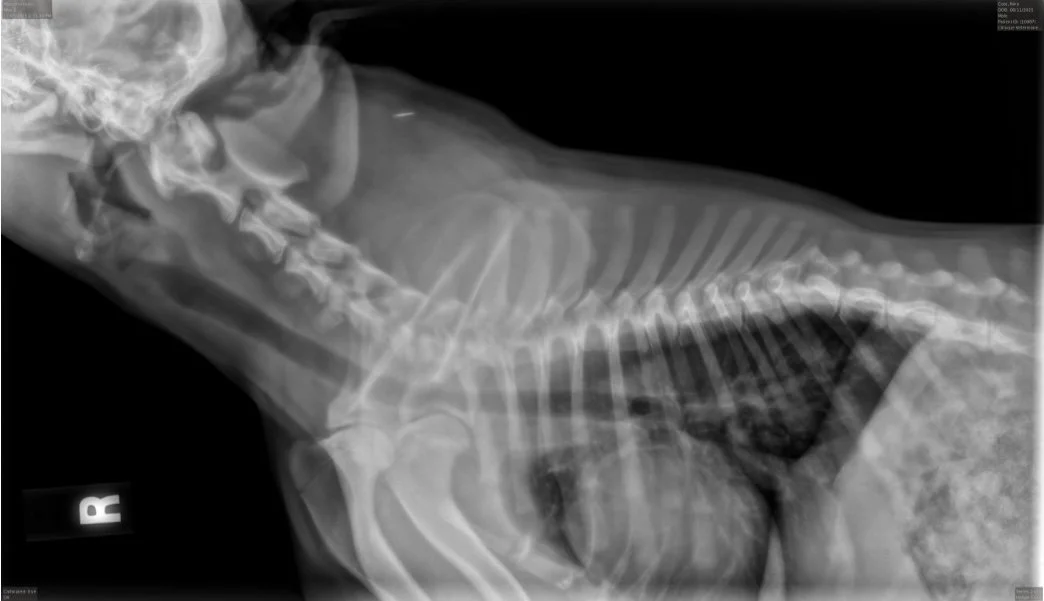

Testés OFA de la race pour Yeux, Hanches, Coudes & Colonne Vertébrale. Les prochains tests se font à l’âge d’un an.